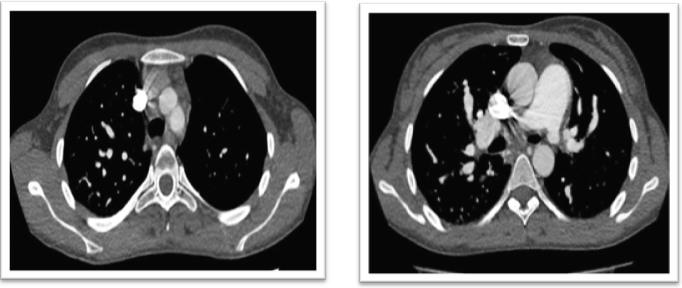

This is a 30-year-old woman with multiple hospitalizations for reporting dyspnea, associated with hemodynamic decompensation, including symptoms of unilateral acute pulmonary oedema (and who has required mechanical respiratory assistance as part of her treatment (Figure 1). She refers to having symptoms since she was 9 years old when she noticed fatigue with usual efforts. Dyspnea was progressive. At the age of 11, she was treated by a pediatric cardiology service where she was diagnosed with stenosis of the left pulmonary artery and underwent balloon angioplasty, after which she was discharged, without being able to record follow-up studies. We consider that the patient was in a stage with few symptoms of her disease and according to her report, she had a normal life. At the age of 22, she suffered a syncope for which she was hospitalized briefly. At the age of 23, during a trip to Peru, she was diagnosed with acute pulmonary oedema associated with altitude. A year later she started with high blood pressure records. The cause of this was the development of severe kidney disease that led to terminal chronic kidney failure (ERSD) Its aetiology could not be determined. She has been undergoing dialysis treatment ever since.

Figure 1

In recent years she has had 5 hospitalizations in our hospital for presenting symptoms and images compatible with unilateral acute pulmonary oedema and one for an alveolar haemorrhage that we interpret as an accident since the patient was anticoagulated due to a PE. She currently has functional class III dyspnea. Her vital signs are, blood pressure 100/50 mm Hg; Heart rate 100/m, regular; Respiratory rate 20/m; SatO2 96% breathing room air; Body mass index 22.8kg/m2. Among her most salient physical data, a well-developed fistula in her right arm stands out. The 2nd heart sound appears to increase, and a 4/6 systolic murmur is heard in the pulmonary focus that radiates to the neck, axilla and interscapular region. She has mild bi-malleolar oedema. In the respiratory system, few dry rales were heard in the suitable base and a slight decrease in the vesicular murmur in the left lung field.